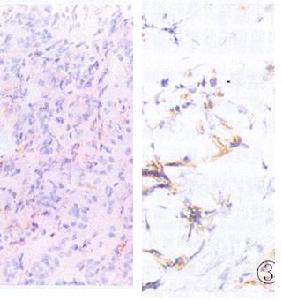

腎活檢:慢性間質性腎炎的組織病理學表現對病因學無特異性。疾病早期,儘管髓旁和髓質區域有嚴重病變,活檢的皮質標本可無異常。當與腎小球腎炎鑑別有困難時,可用腎活檢來排除腎小球腎炎。